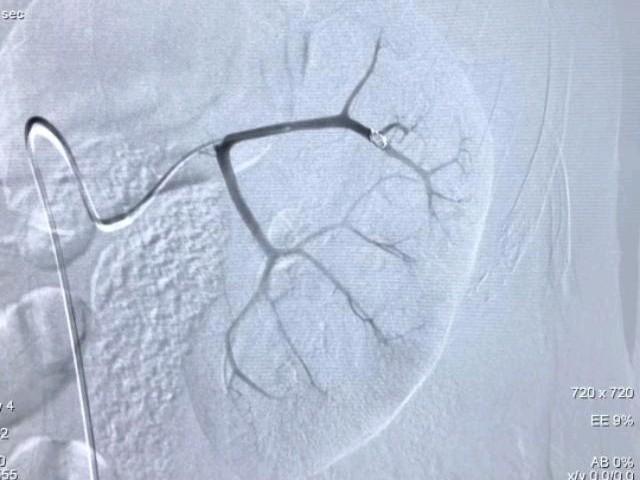

术中造影发现左肾正常形态消失,发现多处血管破裂并伴有造影剂迅速外溢,还在出血,病情非常凶险。夏风飞医生与张主任配合默契,立即应用微导管逐一的对靶向分支血管进行选择造影,查找可能的出血点。采用不同角度,对肾动脉各个分支分别重复造影,术*共中**发现了4条出血血管,在尽量保护仅存的左肾良好组织的前提下,应用微弹圈进行了精确栓塞微创止血治疗。

经持续1个多小时的奋斗,手术非常顺利。血止住了,病人精神状态逐渐改善,生命体征渐趋平稳,安全返回病房进行后续的治疗。脱掉厚重的铅衣后,两位医生才发现里面的手术衣服像水洗一样。

术后24小时,夏风飞医生再次来到病人面前进行查看,患者血压130/80mmHg,肌酐轻度升高,尿管内血尿颜色明显变淡。目前患者左肾已经成功保住,肾功能趋于正常,病情正在有序的恢复中。